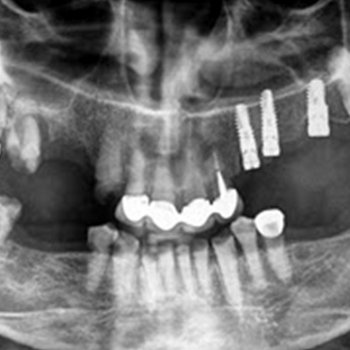

Οι πιο συχνές βλάβες στο στόμα είναι τα αποστήματα, τα οποία όταν οφείλονται σε μικροβιακές λοιμώξεις δοντιών της άνω γνάθου μπορούν να εκδηλώνονται και στην υπερώα (Εικόνα 3). Η θεραπεία τους προϋποθέτει την θεραπεία του υπεύθυνου δοντιού.

Εικόνα 3. α. Απόστημα που οφείλεται σε γομφίο οδόντα (βέλος), β. Απόστημα που οφείλεται σε τομέα οδόντα (βέλος).